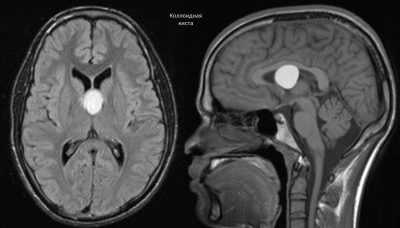

- Магнитно-резонансная томография (или МРТ). Отзывы после проведения данного исследования самые положительные. В большинстве случаев именно с помощью МРТ удалось установить наличие кистозных образований в головном мозге. Метод отличается высокой разрешающей способностью и позволяет успешно выявлять кисты даже самых маленьких размеров. В сложных диагностических случаях прибегают к предварительному введению контраста, позволяющего устанавливать диагноз более точно.